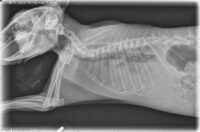

Respiratory

Heart Disease in Companion Rabbits: Causes, Diagnosis, and Treatment

As companion rabbits live longer, the diagnosis of cardiac disease has become more common, influenced by factors such as age, genetics, concurrent diseases, and diet, affecting various parts of the heart including muscles, valves, and electrical conduction.

Thymomas in Rabbits: A Comprehensive Overview

Thymomas are tumors that originate from the thymus, a specialized immune system organ in the chest cavity. While they are relatively rare in rabbits, thymomas represent a significant health concern when they do occur.